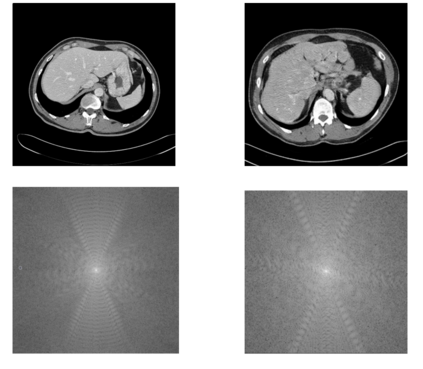

In many clinical settings, the use of both Computed Tomography (CT) and Magnetic Resonance (MRI) is necessary to pursue a thorough understanding of the patient's anatomy and to plan a suitable therapeutical strategy; this is often the case in MRI-based radiotherapy, where CT is always necessary to prepare the dose delivery, as it provides the essential information about the radiation absorption properties of the tissues. Sometimes, MRI is preferred to contour the target volumes. However, this approach is often not the most efficient, as it is more expensive, time-consuming and, most importantly, stressful for the patients. To overcome this issue, in this work, we analyse the capabilities of different configurations of Deep Learning models to generate synthetic CT scans from MRI, leveraging the power of Generative Adversarial Networks (GANs) and, in particular, the CycleGAN architecture, capable of working in an unsupervised manner and without paired images, which were not available. Several CycleGAN models were trained unsupervised to generate CT scans from different MRI modalities with and without contrast agents. To overcome the problem of not having a ground truth, distribution-based metrics were used to assess the model's performance quantitatively, together with a qualitative evaluation where physicians were asked to differentiate between real and synthetic images to understand how realistic the generated images were. The results show how, depending on the input modalities, the models can have very different performances; however, models with the best quantitative results, according to the distribution-based metrics used, can generate very difficult images to distinguish from the real ones, even for physicians, demonstrating the approach's potential.